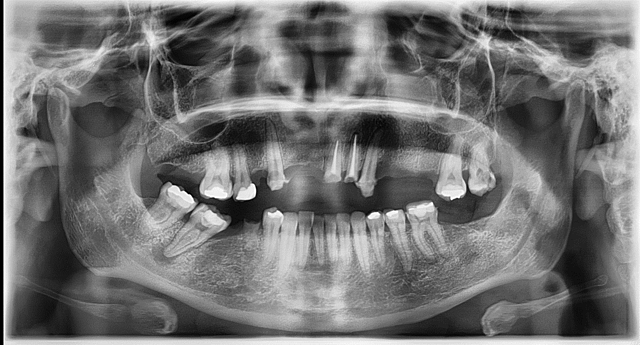

• ORTOPANTOMOGRAFIA

ORTOPANTOMOGRAFIA

Paciente referido a estudio radiologico, para toma ortomantomografica, como apoyo para el diagnostico y plan de tratamiento, esta toma radiologica muestra las estructuras anatomicas de soporte dentario y posicion mandibular del paciente.

• DIAGNOSTICO

DIAGNOSTICO

El paciente ´resenta edentulismo parcial en ambas arcadas poe ausencia de OD. 1.1, 1.2, 1.4., 1.7, 1.8, 2.4, 2.5, 2.6, 3.7, 3.8, y 4.6.

amalgamas filtradas en OD.1.6,2.6,3.4,3.5,4.8.

Endodoncias previamente en OD. 2.1 y 2.2, lesiones apicales en OD. 1.3, 1.6, 2.3, 3.5, 3.6 y 4.1

curacion provisional de HC: filtrada en OD. 3.7. remanente radicular 4.5